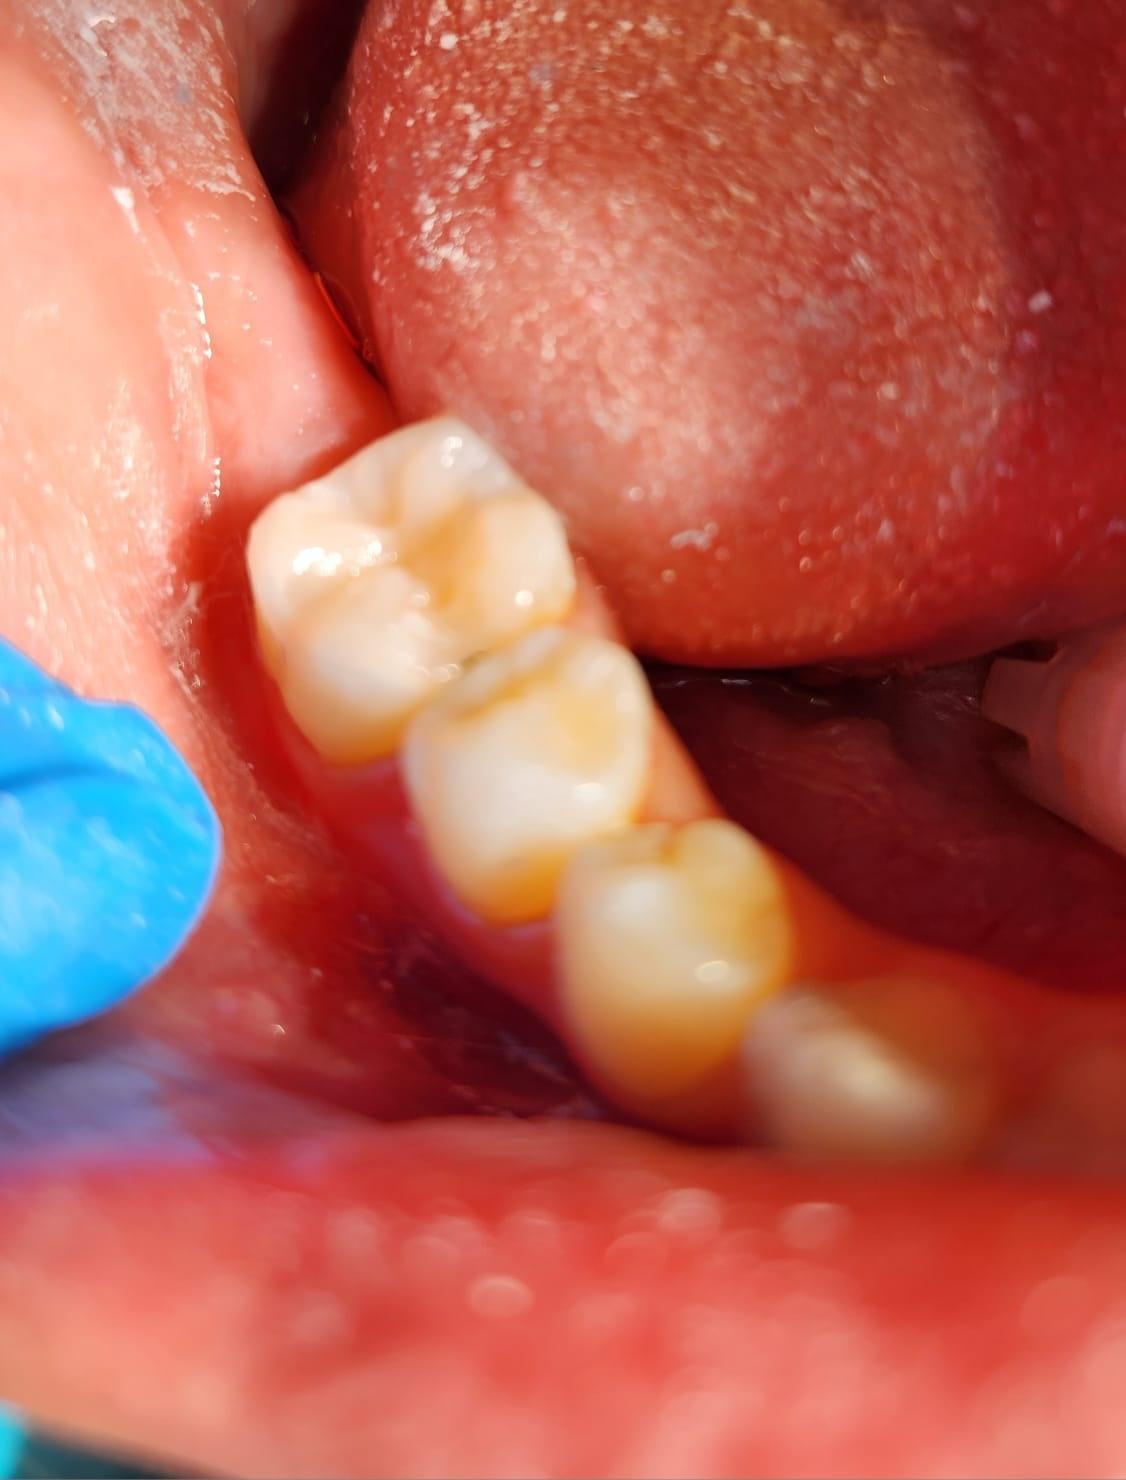

Stresul, fumatul, o igiena dentara precara, dar si modul de alimentatie duc la formarea cariilor. Acestea, netratate, favorizeaza aparitia infectiilor care vor dezvolta chisturi. Astfel de probleme se trateaza cu ajutorul tratamentului endodontic, zona respectiva fiind bine izolata pentru a preveni alte infectii. Atunci cand masurile nu sunt luate din timp, pulpa infectata moare si se formeaza chisturi la nivelul radacinii, iar interventia va deveni mai complexa.

Tratamentul endodontic este mult mai eficient si usor atunci cand bacteriile nu ajung pana in varful radacinii si nu apar chisturile.

La Clinica LUY ESTHETIC ART tratamentul endodontic poate fi efectuat pe durata mai multor sedinte, doar cand chisturile dezvoltate sunt medii. Tratamentul nu este dureros deoarece se realizeaza sub anestezie. Pe langa talent, cunostinte medicale, dar si meticulozitate, acest tratament, presupune folosirea unei aparaturi performante: